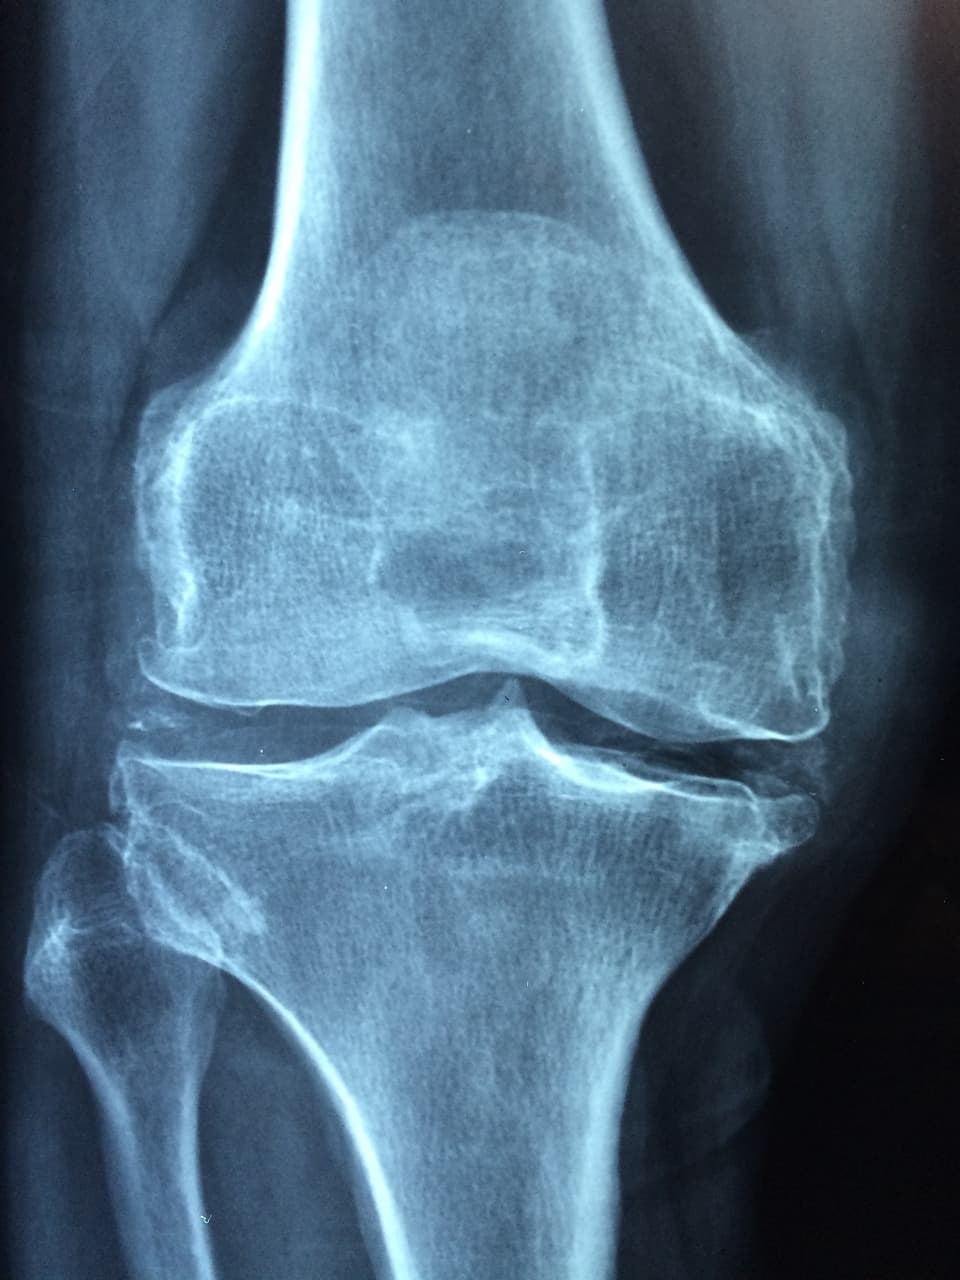

나이가 들수록 몸에서 가장 먼저 신호를 보내는 부위 중 하나가 바로 무릎이다. 무릎 관절은 체중의 하중을 직접적으로 받기 때문에 일상적인 걷기나 계단 오르내리기조차 무리가 될 수 있다. 그런데 많은 사람들이 무릎 통증을 단순한 노화 현상으로 치부하고 방치한다. 하지만 관절은 단순한 뼈의 연결이 아니라, 연골, 인대, 활액 등 다양한 조직이 함께 작동하는 정밀한 구조물이다. 이 구조가 손상되면 회복이 더디고, 치료도 어렵다. 그렇기 때문에 평소 식습관을 통해 무릎 관절을 보호하는 것은 생각보다 훨씬 중요하다.